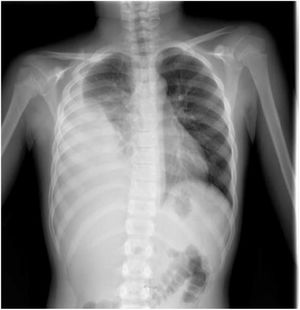

Varón de 10 años que acude por fiebre y tos de una semana de evolución, sin hallazgos en la exploración física se realiza PCR de COVID-19, que es negativa, y se envía a domicilio. A los 12 días reconsulta y en la exploración presenta hipoventilación en hemitórax derecho. En la analítica sanguínea destaca una PCR 123 mg/L; LDH 327 U/L; coagulación con: TP 58% y dímero D 5.825 ng/mL. Test rápido (ICT) con resultado positivo y PCR negativa. En la radiografía de tórax (fig. 1), se observa opacidad extensa en el hemitórax derecho con derrame pleural ocupando aproximadamente el 50% del mismo. En la ecografía torácica se comprueba derrame pleural de 7,5 cm de grosor en base pulmonar (fig. 2). Ante sospecha de COVID-19 grave, se inicia antibioterapia i.v., dosis de vitamina K y heparinas de bajo peso molecular (HBPM). A las 48 h presenta necesidad de oxígeno y empeoramiento del derrame. Se coloca drenaje pleural. El análisis bioquímico del líquido pleural presentaba leucocitos 588/uL con 93% de linfocitosis, ADA 200, proteínas 5,7 g/dL, LDH 718. Se establece diagnóstico de presunción de tuberculosis. Se realizan pruebas Mantoux (25 mm a las 72 h) (fig. 3) y QuantiFERON, que son positivas. Recibe tratamiento antituberculoso con isoniazida, rifampicina, pirazinamida y etambutol durante dos meses, seguido de cuatro meses con isoniazida y rifampicina. La evolución del paciente es favorable, se solicita test serológico ELISA, encontrándose IgG e IgM negativas.

Estudios de imagen. Radiografía simple de tórax. Opacidad extensa en el hemitórax derecho con semiología de derrame pleural (ocupando aproximadamente el 50% del hemitórax), con imágenes compatibles con condensación alveolar en campo medio del pulmón. Ausencia de imágenes derrame pleural o condensaciones en parénquima pulmonar izquierdo.